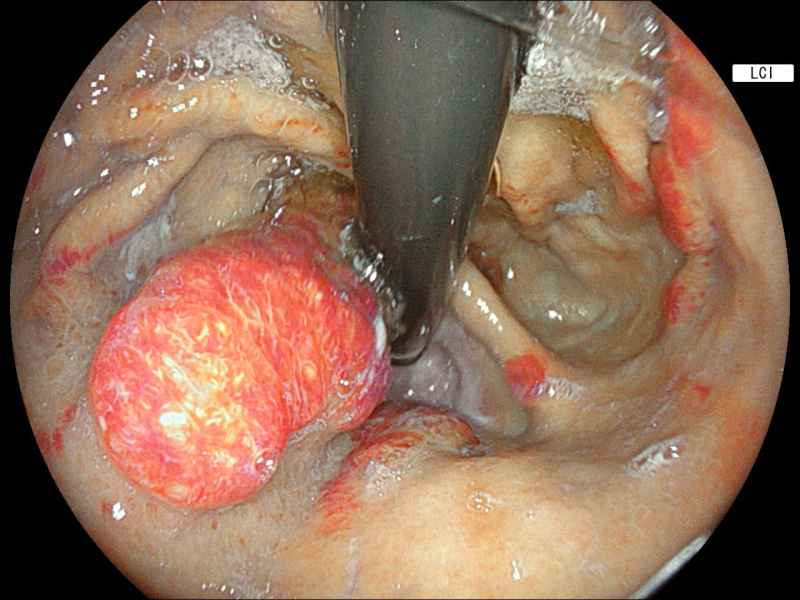

Behind an adherent clot

Fotografia